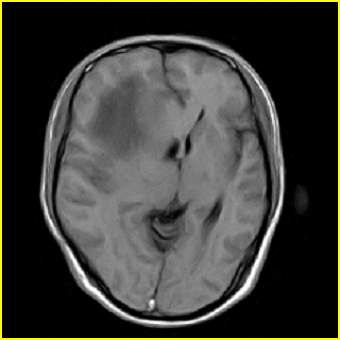

男,45岁,头部剧烈疼痛伴呕吐5天。

右侧额叶见较大的类圆形长t1信号环绕等t1环影,长t2信号环绕短等t2环,周围见明显水肿占位征,中线结构左移,男,45岁,头部剧烈疼痛伴呕吐5天。

右侧额叶,见一占位病灶,t1像病灶、水肿长t1;其间为短t1环行信号。t2像病灶、水肿长t2,其间为短t2环行信号。占位效应明显,中线左移,右测脑室受压闭塞。结合患者发病较急。首先考虑:右侧额叶脑脓肿形成。鉴别:1、转移瘤,多发多见2、胶质瘤。建议增强

t1加权肿瘤呈低信号,肿瘤壁呈等信号.t2 加权时肿瘤呈高信号,肿瘤壁呈等信号.

考虑1脑脓肿.2恶性胶质瘤.